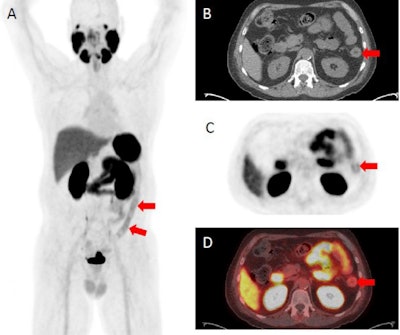

F-18 DCFPyL PET/CT demonstrating abnormally increased uptake in the descending colon (identified by red arrows), sigmoid colon, and rectum corresponding to findings on endoscopy. (A) F-18 DCFPyL PET/CT uptake in the descending colon on a coronal plane. (B) Axial CT image with arrows identifying active inflammation in the descending colon. (C) Axial PET imaging arrows identifying active inflammation in the descending colon. (D) Axial F-18 DCFPyL PET/CT fusion imaging identifying active inflammation in the descending colon. Image courtesy of Clinical and Experimental Gastroenterology.